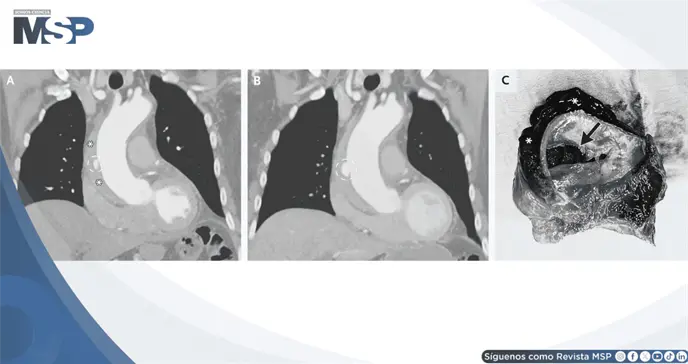

La TC evidenció una proyección ulcerada en la aorta torácica ascendente, asociada a un hematoma intramural que se extendía hacia el arco aórtico y la porción proximal de la aorta descendente.

Tres días después, una TC de control mostró aumento del tamaño de la proyección ulcerada. Se realizó entonces una sustitución abierta supracoronaria de la aorta ascendente y del hemiarco. Durante el procedimiento se identificaron un desgarro intimal y una disección de la aorta ascendente, además del hematoma intramural.